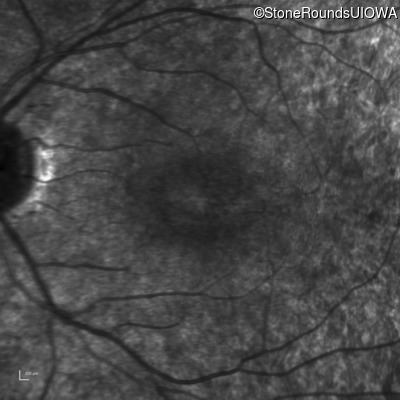

Infrared Fundus Photograph - Right - 20/25 -2

Exemplar